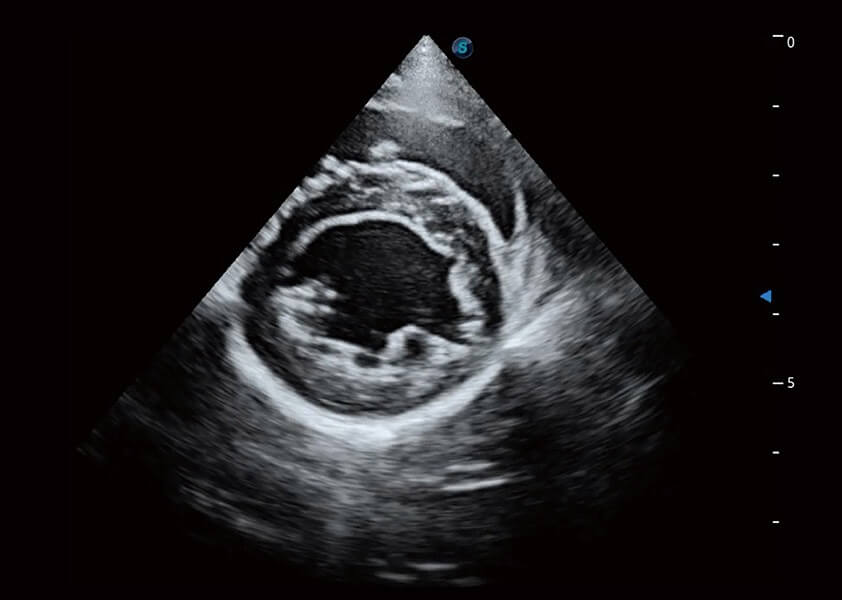

ProPet 60 作为一款高端台式动物超声设备,为动物医生的日常诊断提供了一系列贴合动物临床需求、解决临床实际问题的高级成像功能。凭借全系列高清探头,满足医生对腹部、心脏、生殖、浅表、肌骨等成像的所有需求,切实帮助您提升检查效率,提高诊断信心。

动物是人类最亲密的朋友和最值得信赖的伙伴。MILE米乐集团官网也一直致力于探索动物专用的超声影像解决方案。 全新推出的ProPet系列,是MILE米乐集团官网在动物超声影像智能化、专业化、精准化的一次跨越式革新。动物不能用言语来表述自己的不适,通过超声影像,ProPet系列搭建了动物医生与不同物种沟通的“桥梁”,为动物医生注入了“治愈之力”。